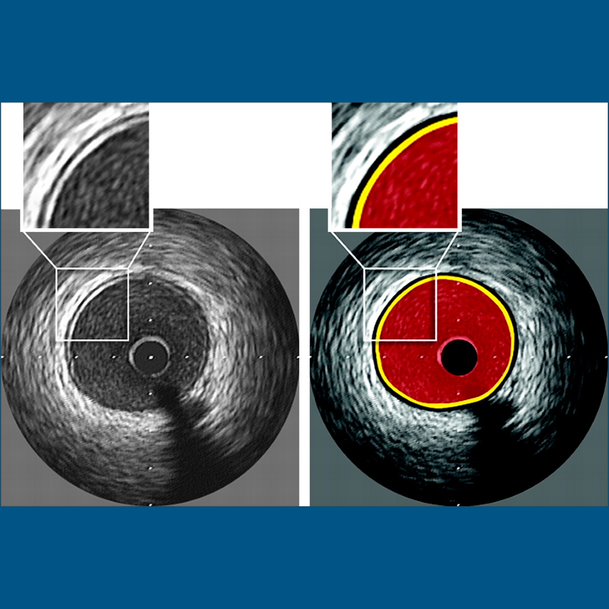

Intravascular Ultrasound is a medical imaging methodology using a specially designed catheter with a miniaturized ultrasound probe attached to the distal end of the catheter.

Intravascular Ultrasound is done routinely through a catheter to identify the complexities, dissections, calcium contents in the coronary plaques. This helps our cardiologists in improving the patient safety.